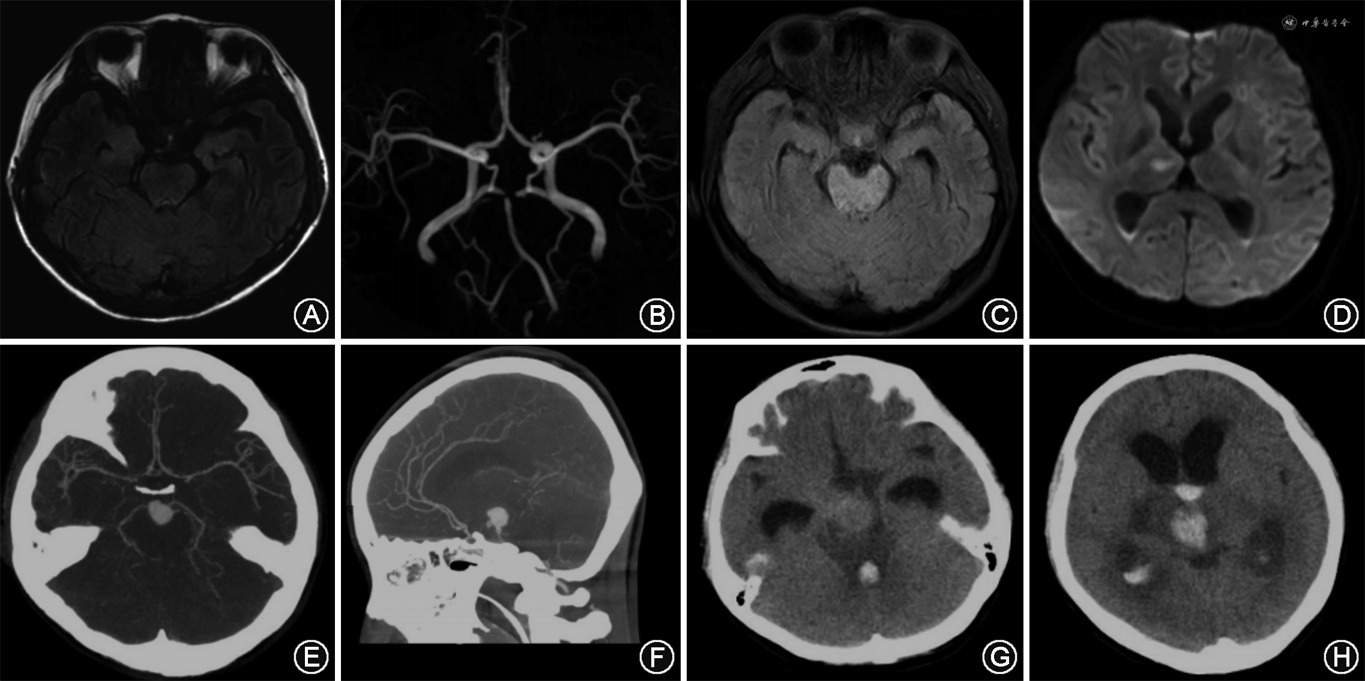

临床资料 患者女性,28岁,因“发热2周,突发意识障碍1 d”于2019年12月29日入院。患者入院前2周感冒后出现咳嗽、发热,体温最高达38.5 ℃,给予抗炎、抗病毒治疗1周后,症状减轻。入院前1 d出现左侧舌面部麻木,伴双下肢无力,就诊于当地医院,行颅脑MRI提示脑内多发异常信号影(图1A),考虑炎性可能性大,颅脑MRA提示基底动脉尖部信号缺失,双侧大脑后动脉由后交通动脉代偿供血(图1B)。之后患者逐渐出现意识障碍,为求进一步诊治,急诊以“颅内感染”收入我院。患者既往个人史、家族史无特殊。入院后体格检查:体温38.7 ℃,心率105次/min,呼吸18次/min,血压107/80 mmHg(1 mmHg=0.133 kPa),浅昏迷,轻度贫血貌,压眶刺激有去大脑强直表现,四肢腱反射活跃,双侧病理征阳性,颈抵抗,其余神经系统检查不能合作。辅助检查:白细胞14.97×109/L(正常值3.50×109/L~9.50×109/L),中性粒细胞百分比0.88(正常值0.40~0.75),红细胞3.11×1012/L(正常值3.80×1012/mm3~5.10×1012/mm3),血红蛋白86 g/L(正常值115~150 g/L)。红细胞沉降率102 mm/h(正常值0~15 mm/h)。C反应蛋白112.0 mg/L(正常值0~3.5 mg/L)。腰椎穿刺脑脊液压力320 mmH2O(1 mmH2O=0.009 8 kPa),外观淡黄色稍混浊,蛋白定量1.64 g/L(正常值0.15~0.45 g/L),潘氏反应(+),氯化物133 mmol/L(正常值119~129 mmol/L),葡萄糖0.2 mmol/L(正常值2.3~4.1 mmol/L),白细胞总数 591×106/L(正常值0~8×106/L),免疫球蛋白IgG 292 mg/L(正常值0~34 mg/L)。血培养:草绿色链球菌(+)。超声心动图提示二尖瓣轻度关闭不全,二尖瓣前叶及后叶赘生物形成。颅脑MRI提示脑桥及右侧颞顶枕交界区多发异常信号影,考虑炎性可能性大,右侧丘脑急性脑梗死,蛛网膜下腔出血,桥前池、大脑脚间池血肿,双侧脑室后角积血(图1C、D)。颅脑增强CT及颅脑CTA提示基底动脉尖动脉瘤,大小约11.1 mm×15.0 mm,伴周围出血(图1E、F)。患者初步诊断为感染性心内膜炎、感染性颅内动脉瘤、细菌性脑膜脑炎、脑梗死、脑出血、蛛网膜下腔出血。

入院后给予万古霉素1 g/12 h及美罗培南2 g/8 h抗感染及甘露醇50 g/8 h 静脉滴注脱水降颅压等对症治疗。入院后第11天,再次行腰椎穿刺,脑脊液压力300 mmH2O,外观血性,蛋白定量2.15 g/L,潘氏反应(++),葡萄糖0.9 mmol/L,白细胞总数165×106/L,红细胞总数14 000×106/L,IgG 335 mg/L,同时送检脑脊液病原体微生物学检查,结果提示草绿色链球菌属(+)。根据药敏结果,将抗生素调整为利奈唑胺和美罗培南。入院后第15天,患者突然出现心率减慢、双侧瞳孔散大,急查颅脑CT示第三脑室、第四脑室、侧脑室后角积血较前增多,侧脑室扩大(图1G、H),考虑急性梗阻性脑积水。随后,患者呼吸、心搏骤停,给予心肺复苏术、气管插管、呼吸机辅助呼吸,并同时于床头行脑室外引流术。数小时后,患者再次突发血氧、血压下降,最终死于颅内动脉瘤破裂出血造成梗阻性脑积水后导致的脑疝。